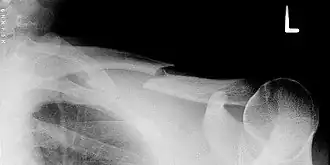

![]() Radiografía de una fractura completa de la clavícula del hombro izquierdo. | ||

Las fracturas de la clavícula implican aproximadamente el 5% de todas las fracturas vistas en las emergencias de los hospitales.[1] Por lo general, la fractura ocurre entre el segmento 2/3 proximal (cercano a la línea media del cuerpo) y el tercio distal (alejado de la línea media del cuerpo) de la longitud de la clavícula. Los lactantes y niños son particularmente propensos a este tipo de fracturas. Las fracturas de la clavícula puede presentarse en el período neonatal, especialmente después de un parto dificultoso.[2]

Aproximadamente el 80% de las fracturas de la clavícula se producen en el tercio medio del recorrido del hueso, 15% con asociación de la parte distal o el tercio lateral, y un 5% de asociación del tercio proximal o medial.[1]